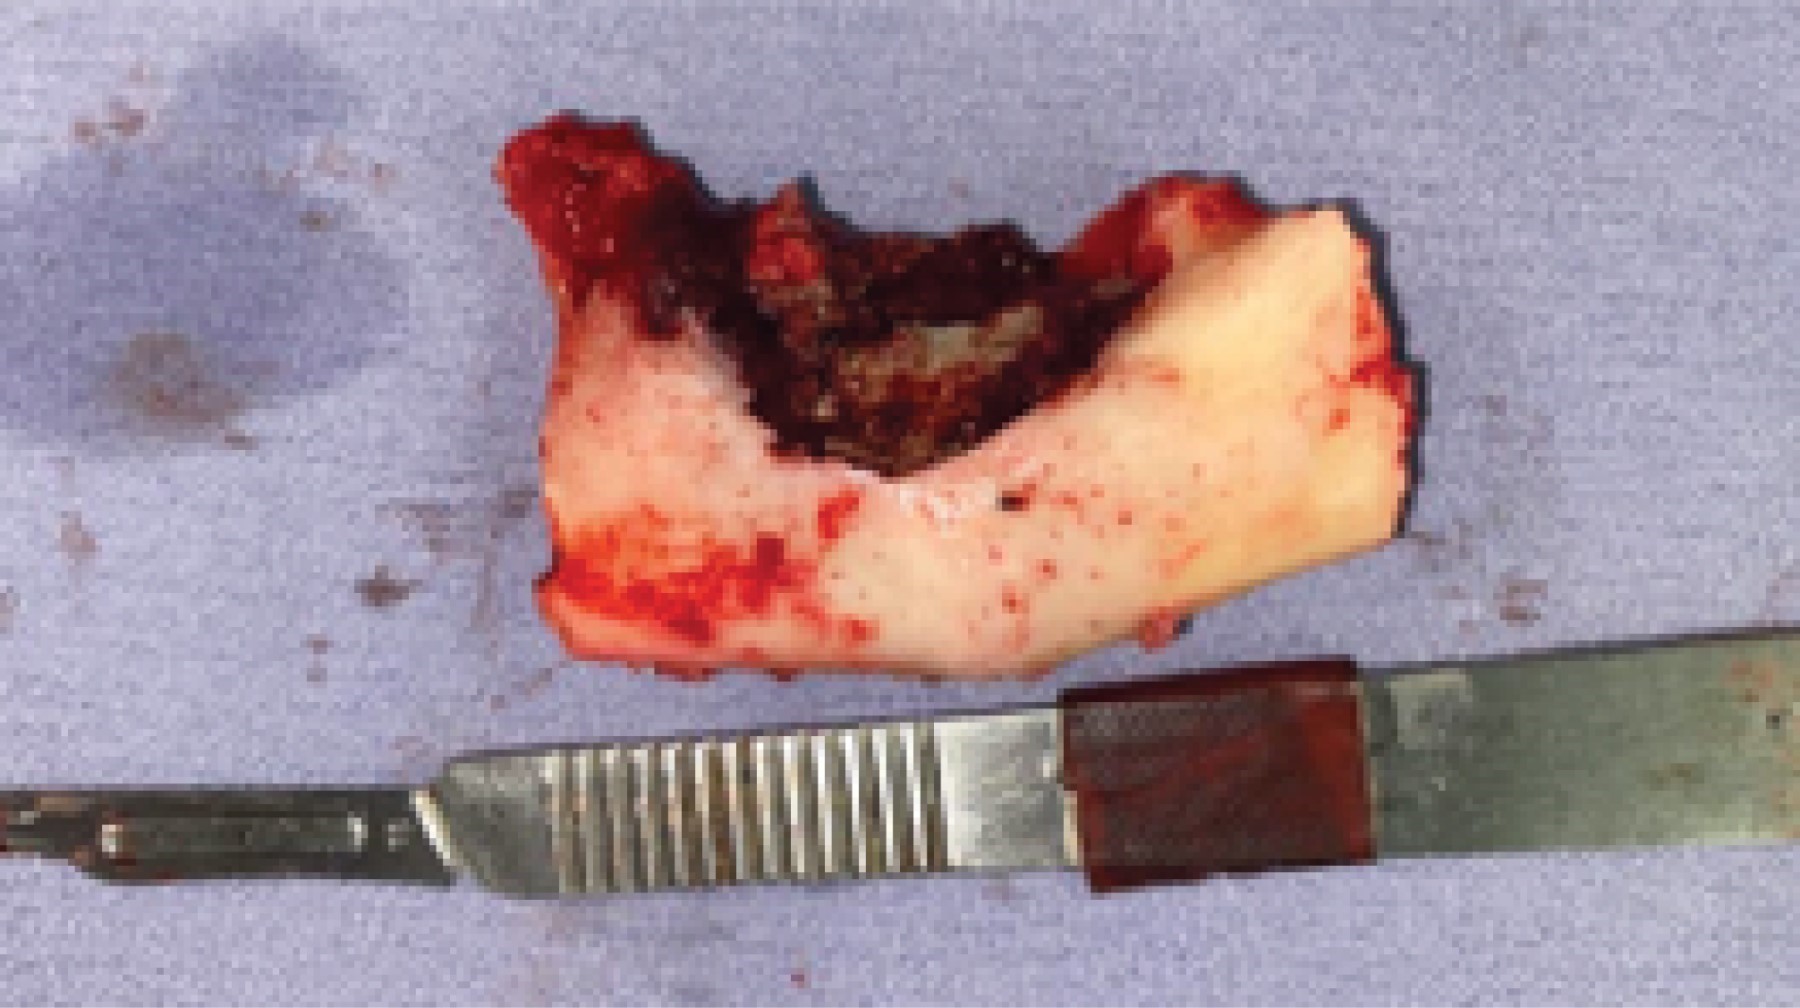

Bajo anestesia general balanceada con intubación nasotraqueal, se realizó asepsia y antisepsia de la zona a intervenir. Se hizo abordaje extraoral tipo Risdon con extensión submental, se expuso en su totalidad hemimandíbula izquierda (Figura 5). Se colocó y fijó placa de reconstrucción 2.4 alto perfil, la cual fue predoblada con la estereolitografía y esterilizada. Se fijó placa con cinco tornillos 2.4 bicorticales en el segmento proximal y cuatro tornillos 2.4 bicorticales en el segmento distal, todos los tornillos utilizados fueron bloqueados. Diez días previos al procedimiento se inició manejo con doxiciclina 300 mg cada 12 horas según el protocolo descrito por Putke y colegas, de técnica de fluorescencia transoperatoria (Figura 6). Posterior a esto se realizó la resección en bloque con bordes óseos sanos según lo planeado tomográficamente y lo visto clínicamente con la técnica de fluorescencia (Figura 7). Se colocaron múltiples membranas de plasma rico en factores de crecimiento (Figura 8) y se realizó hemostasia, cierre por planos hacia el piso de la boca y de abordaje de Risdon y se colocó Penrose de abordaje cervical. Se dio por terminado el procedimiento quirúrgico, enviando pieza quirúrgica a patología (Figura 9). La paciente cursó con un postoperatorio adecuado (Figura 10).

Figura 8

Figura 9